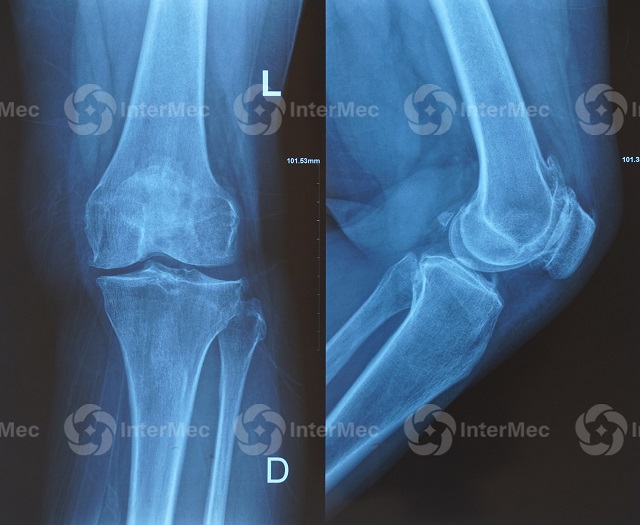

3. Chẩn đoán hình ảnh

- X-quang: Phát hiện hẹp khe khớp, gai xương, tổn thương xương.

- MRI: Đánh giá chi tiết sụn, dây chằng, tình trạng phù xương, tổn thương sớm chưa thể hiện trên X-quang.

- Siêu âm: Kiểm tra tràn dịch, viêm màng hoạt dịch, kén Baker và hỗ trợ các thủ thuật như chọc hút, tiêm khớp.

Kết hợp các kỹ thuật này giúp bác sĩ xác định chính xác nguyên nhân viêm khớp gối và đưa ra phác đồ điều trị hiệu quả nhất.